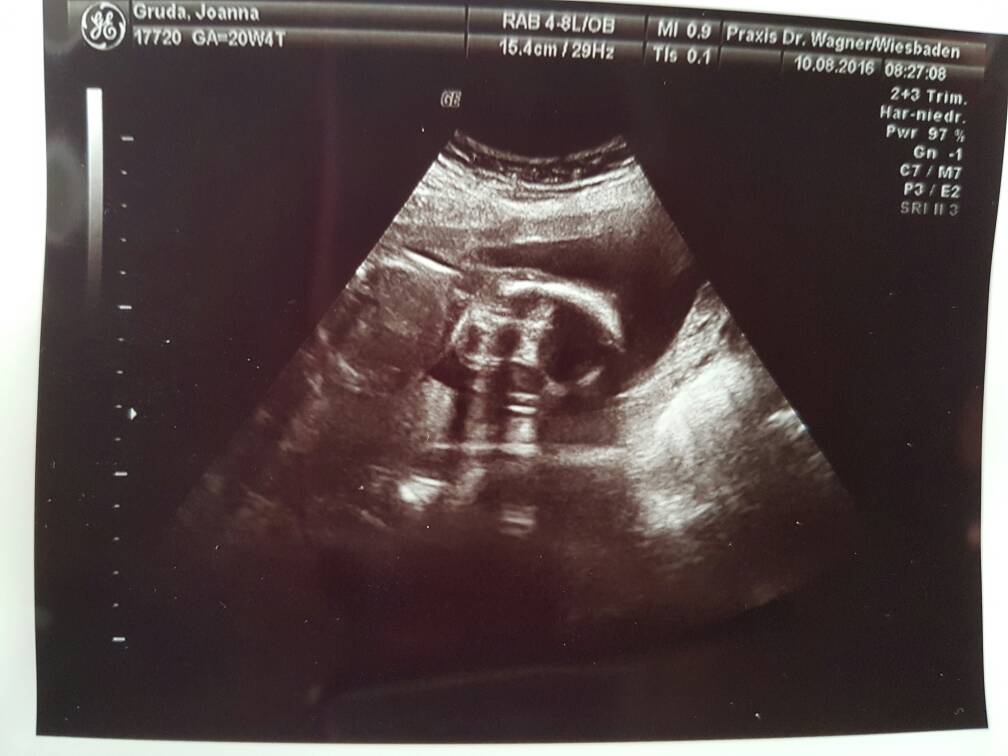

Tak wiec moje dziecko waxy 450g [emoji7][emoji41] w 21 tygodniu. Takze pieknie sie rozwija. Wszystkie wymiary w normie.pepowina ok , lozysko ok, wszystkie przeplywy w normie , serce z Lewej strony , bicie prawidlowo, pecherz uwidoczniono. Tyle co zapamietalam . Musze przetlymaczyc kilka skrotow z muterrpass z usg bo nie jarze po niemiecku a cos mi powpisywal.

Dziec jest ulozony na dzien dzisiejszy glowkowo z Lewej strony trzymaly nogi i jest odwrocony plecami wiec boksuje mi kregoslup.

Oczywiscie standardowo kurde nie chcialo sie pokazac, zle ulozone wiec ciezko mu bylo bombardowac mnie to glowica od usg.przeprosil nas I powiedzial ze no tak ulozone ze nie zobaczy Dokladnie ale pokombinowal I przedstawiam Wam drogie ciocie LENE MARTE , ktora za tydzien moze byc FABIANEM bo matka czuje Nadal ze ma chlopca I idzie w Pl na usg4d w celu potwierdzenia .Pozwolil nam jechac do Pl mam Robic Czeste przystanki nie trzymac siku I Duzo pic. Szyjka zamknieta I dluga. Wyniki super .

Oto LENA MARTA na dzien dzisiejszy.